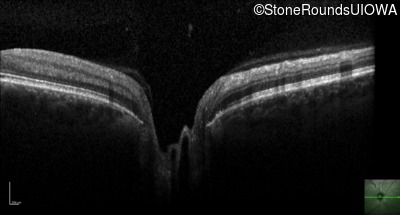

Leber Hereditary Optic Neuropathy (IIIC1c)

OCT Stack

Leber Hereditary Optic Neuropathy

MT-ND6

14484 T>C

MT